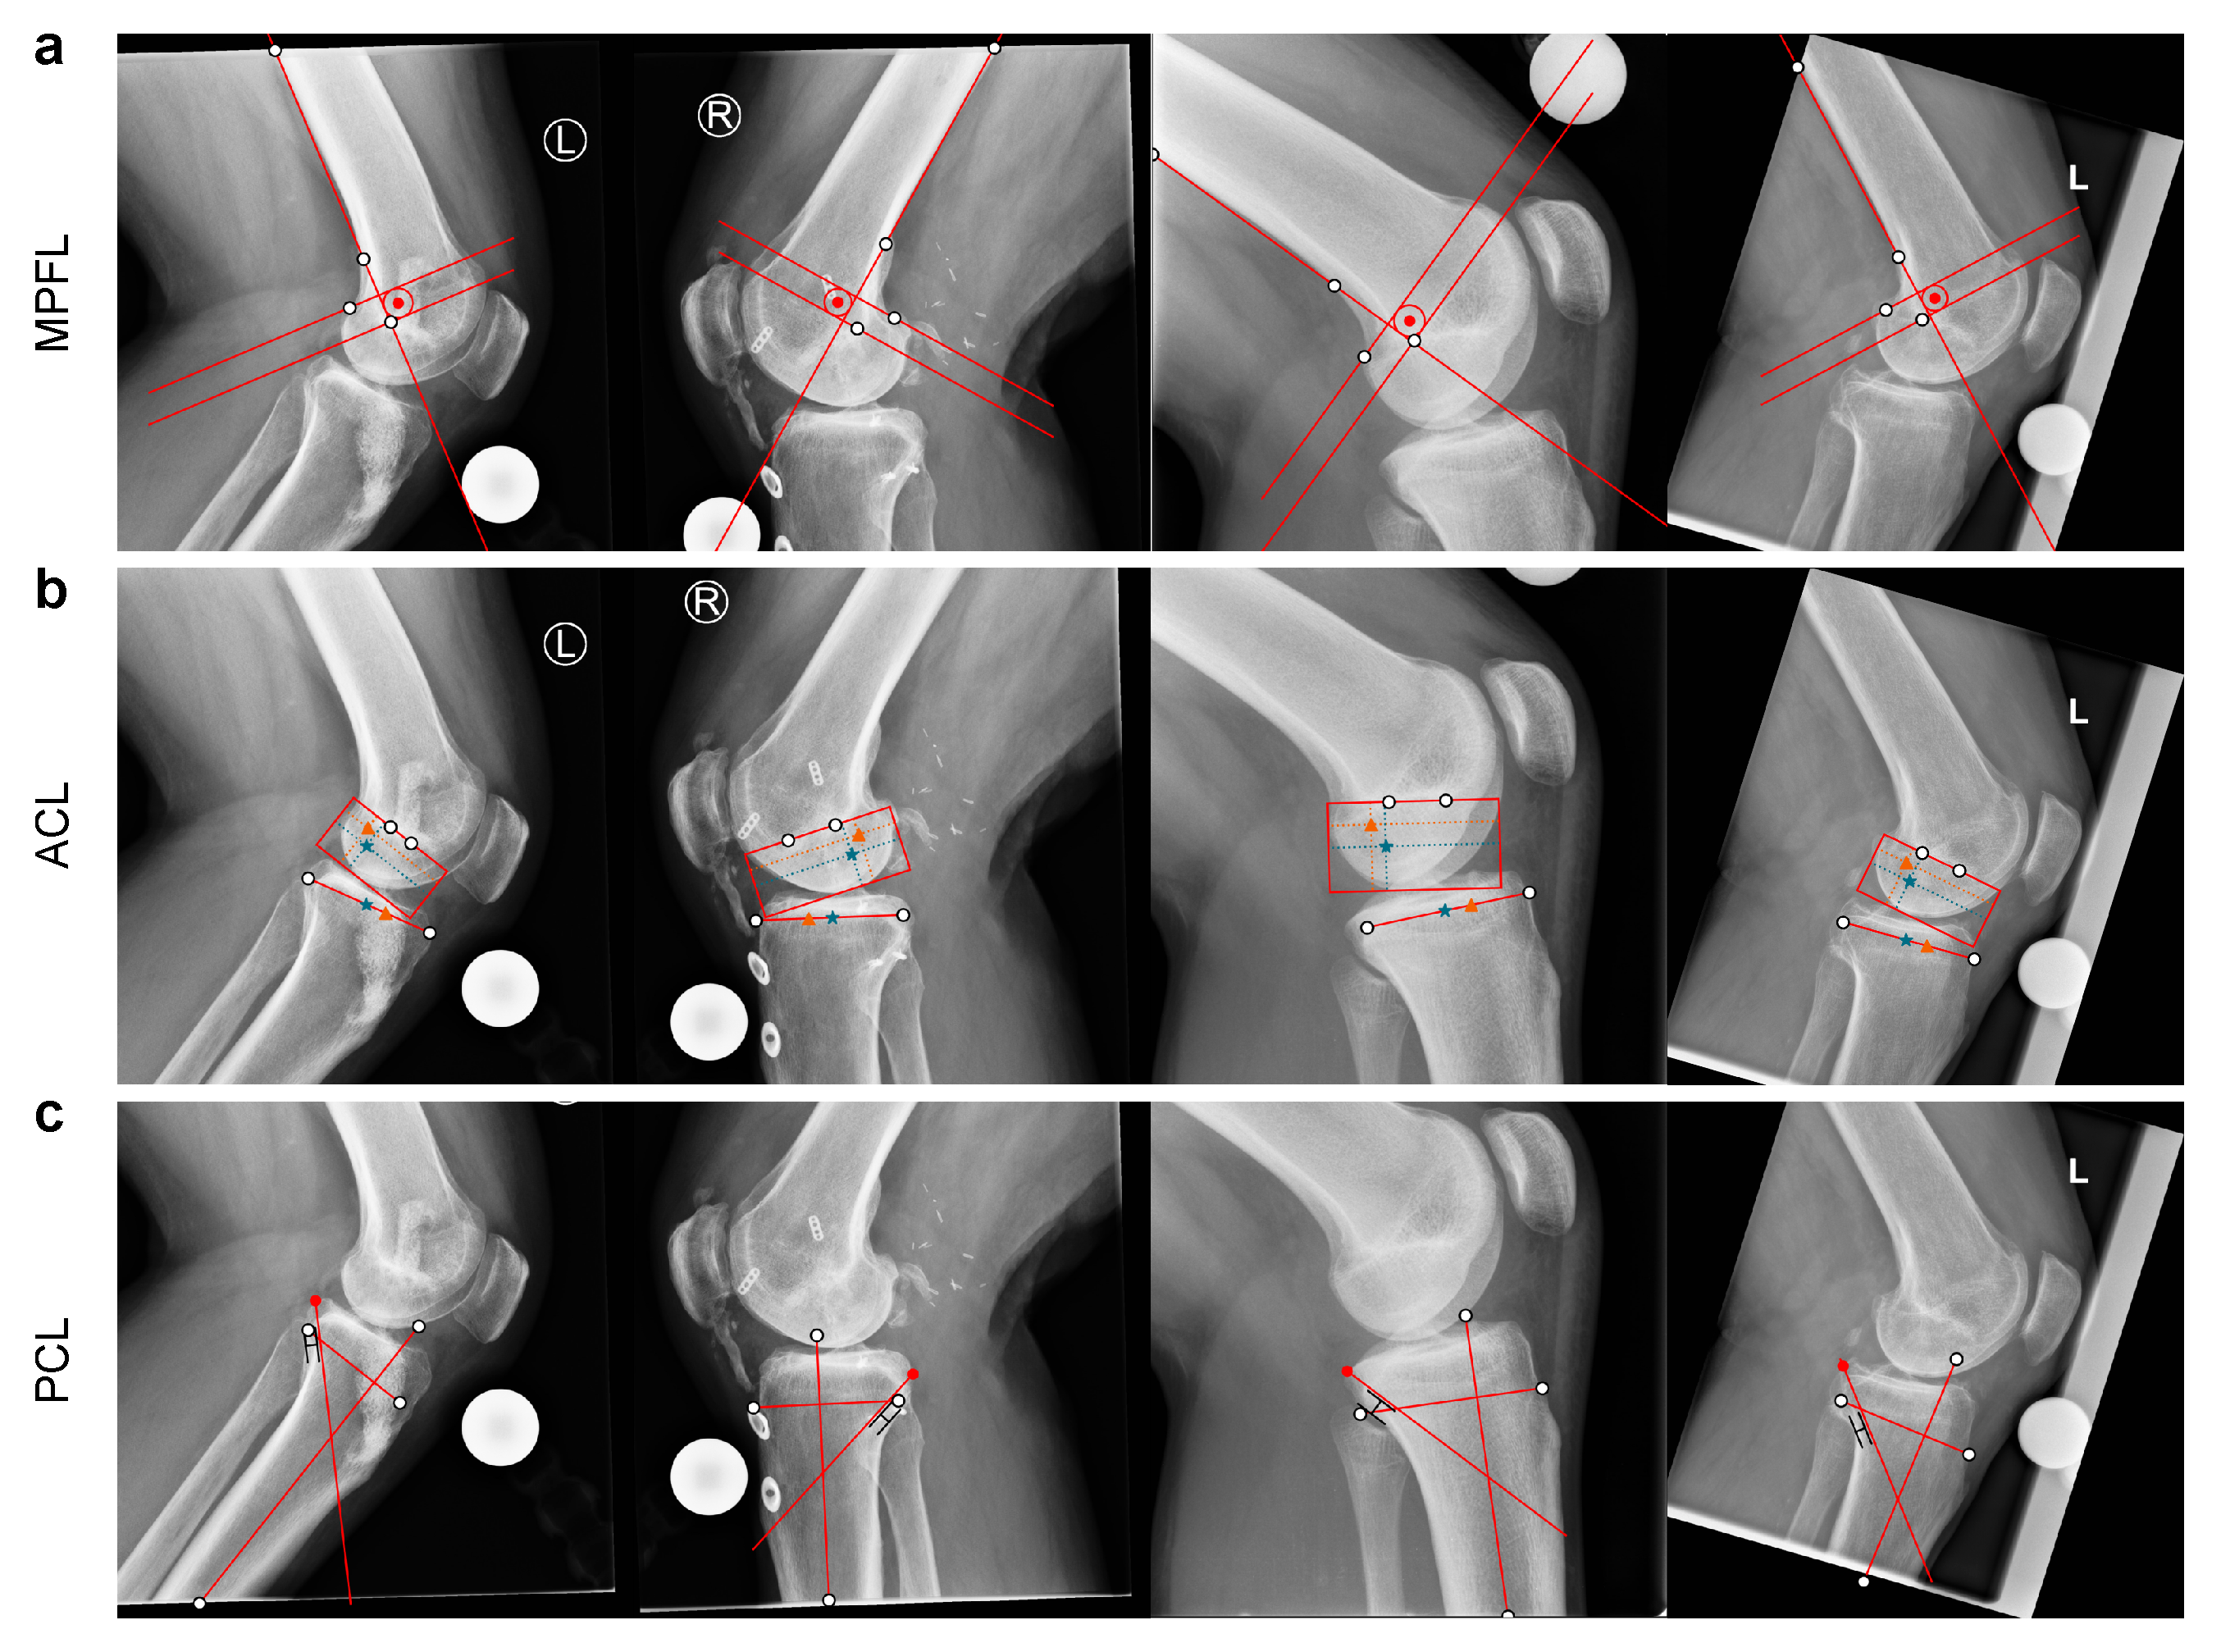

Appendix A. Pre-Operative Planning Examples

Appendix B.1. MPFL Reconstruction

Appendix B.2. ACL Reconstruction

Appendix B.3. PCL Reconstruction